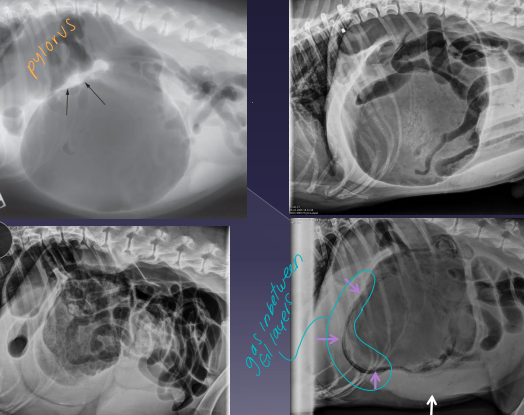

Gastric Dilatation-Volvulus (GDV)

Et: pylorus moves R → ventral → L → dorsal

Dt: lactate trends, ECG (VPC), PT/PTT, RL rads w/ double bubble

Tx: gastric decompress (Trocarization, OG tube), right gastropexy, de-rotation, tube feed, famotidine, pantoprazole, mu opioids, fluids, O2

** Stand on left side, R hand pylorus, L hand on top of fundus - then rotate **